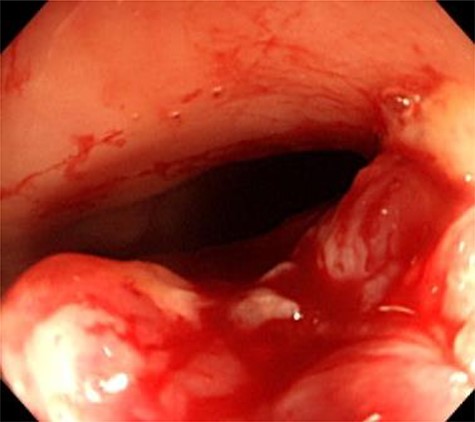

the uterus and rectum (Fig. 2A). The computed tomography scan showed expansion of the intestines and no evidence of free intraperitoneal air (Fig. 2B). As she had a history of bloody stool and the CEA level was increased, we performed colonoscopy, which showed a malignant tumor of the rectum (Fig. 3). The protruding tumor was located 7 cm from the anus. Exploratory laparotomy showed a 90-mm pelvic mass involving the uterus, ileum and rectum. Therefore, we performed an en bloc resection of the mass, including total hysterectomy, bilateral salpingo-oophorectomy, partial resection of the ileum and the Hartmann operation. Macroscopically, the resected pelvic mass invaded the uterus, intestine and rectum, and a colouterine fistula was identified (Fig. 4). The main portion of the tumor was located in the rectum, and it grossly appeared that tumor invasion occurred from the rectum to the uterus and ileum. Microscopic examination of the pelvic mass showed complicated glandular structures in a desmoplastic stroma. The cells forming the lumen were primarily columnar epithelium, consistency of the small glandular cavity was high and severe dyskaryotic cells were multilayered. The nuclei were enlarged and irregularly shaped, contained coarse chromatin and showed atypia. Immunohistochemical staining was performed. Cytokeratin (CK)20 (Dako), NCL-Villin (Novocastra) and CEA (Dako) were positive, and CK7 (Dako) was negative. The final diagnosis was moderately differentiated tubular adenocarcinoma of the rectum, stage IIC, pT4b N0 M0. The patient’s postoperative course was uneventful. The serum level of CEA returned within normal range 1 month postoperatively. Adjuvant chemotherapy (TS-1) was administered for 6 months postoperatively. The patient has been followed up with for >12 months without any signs of recurrence.

Colonoscopy findings. Colonoscopy showed a malignant tumor of the rectum. The tumor was localized, and invasion outside the colonic wall was suspected.